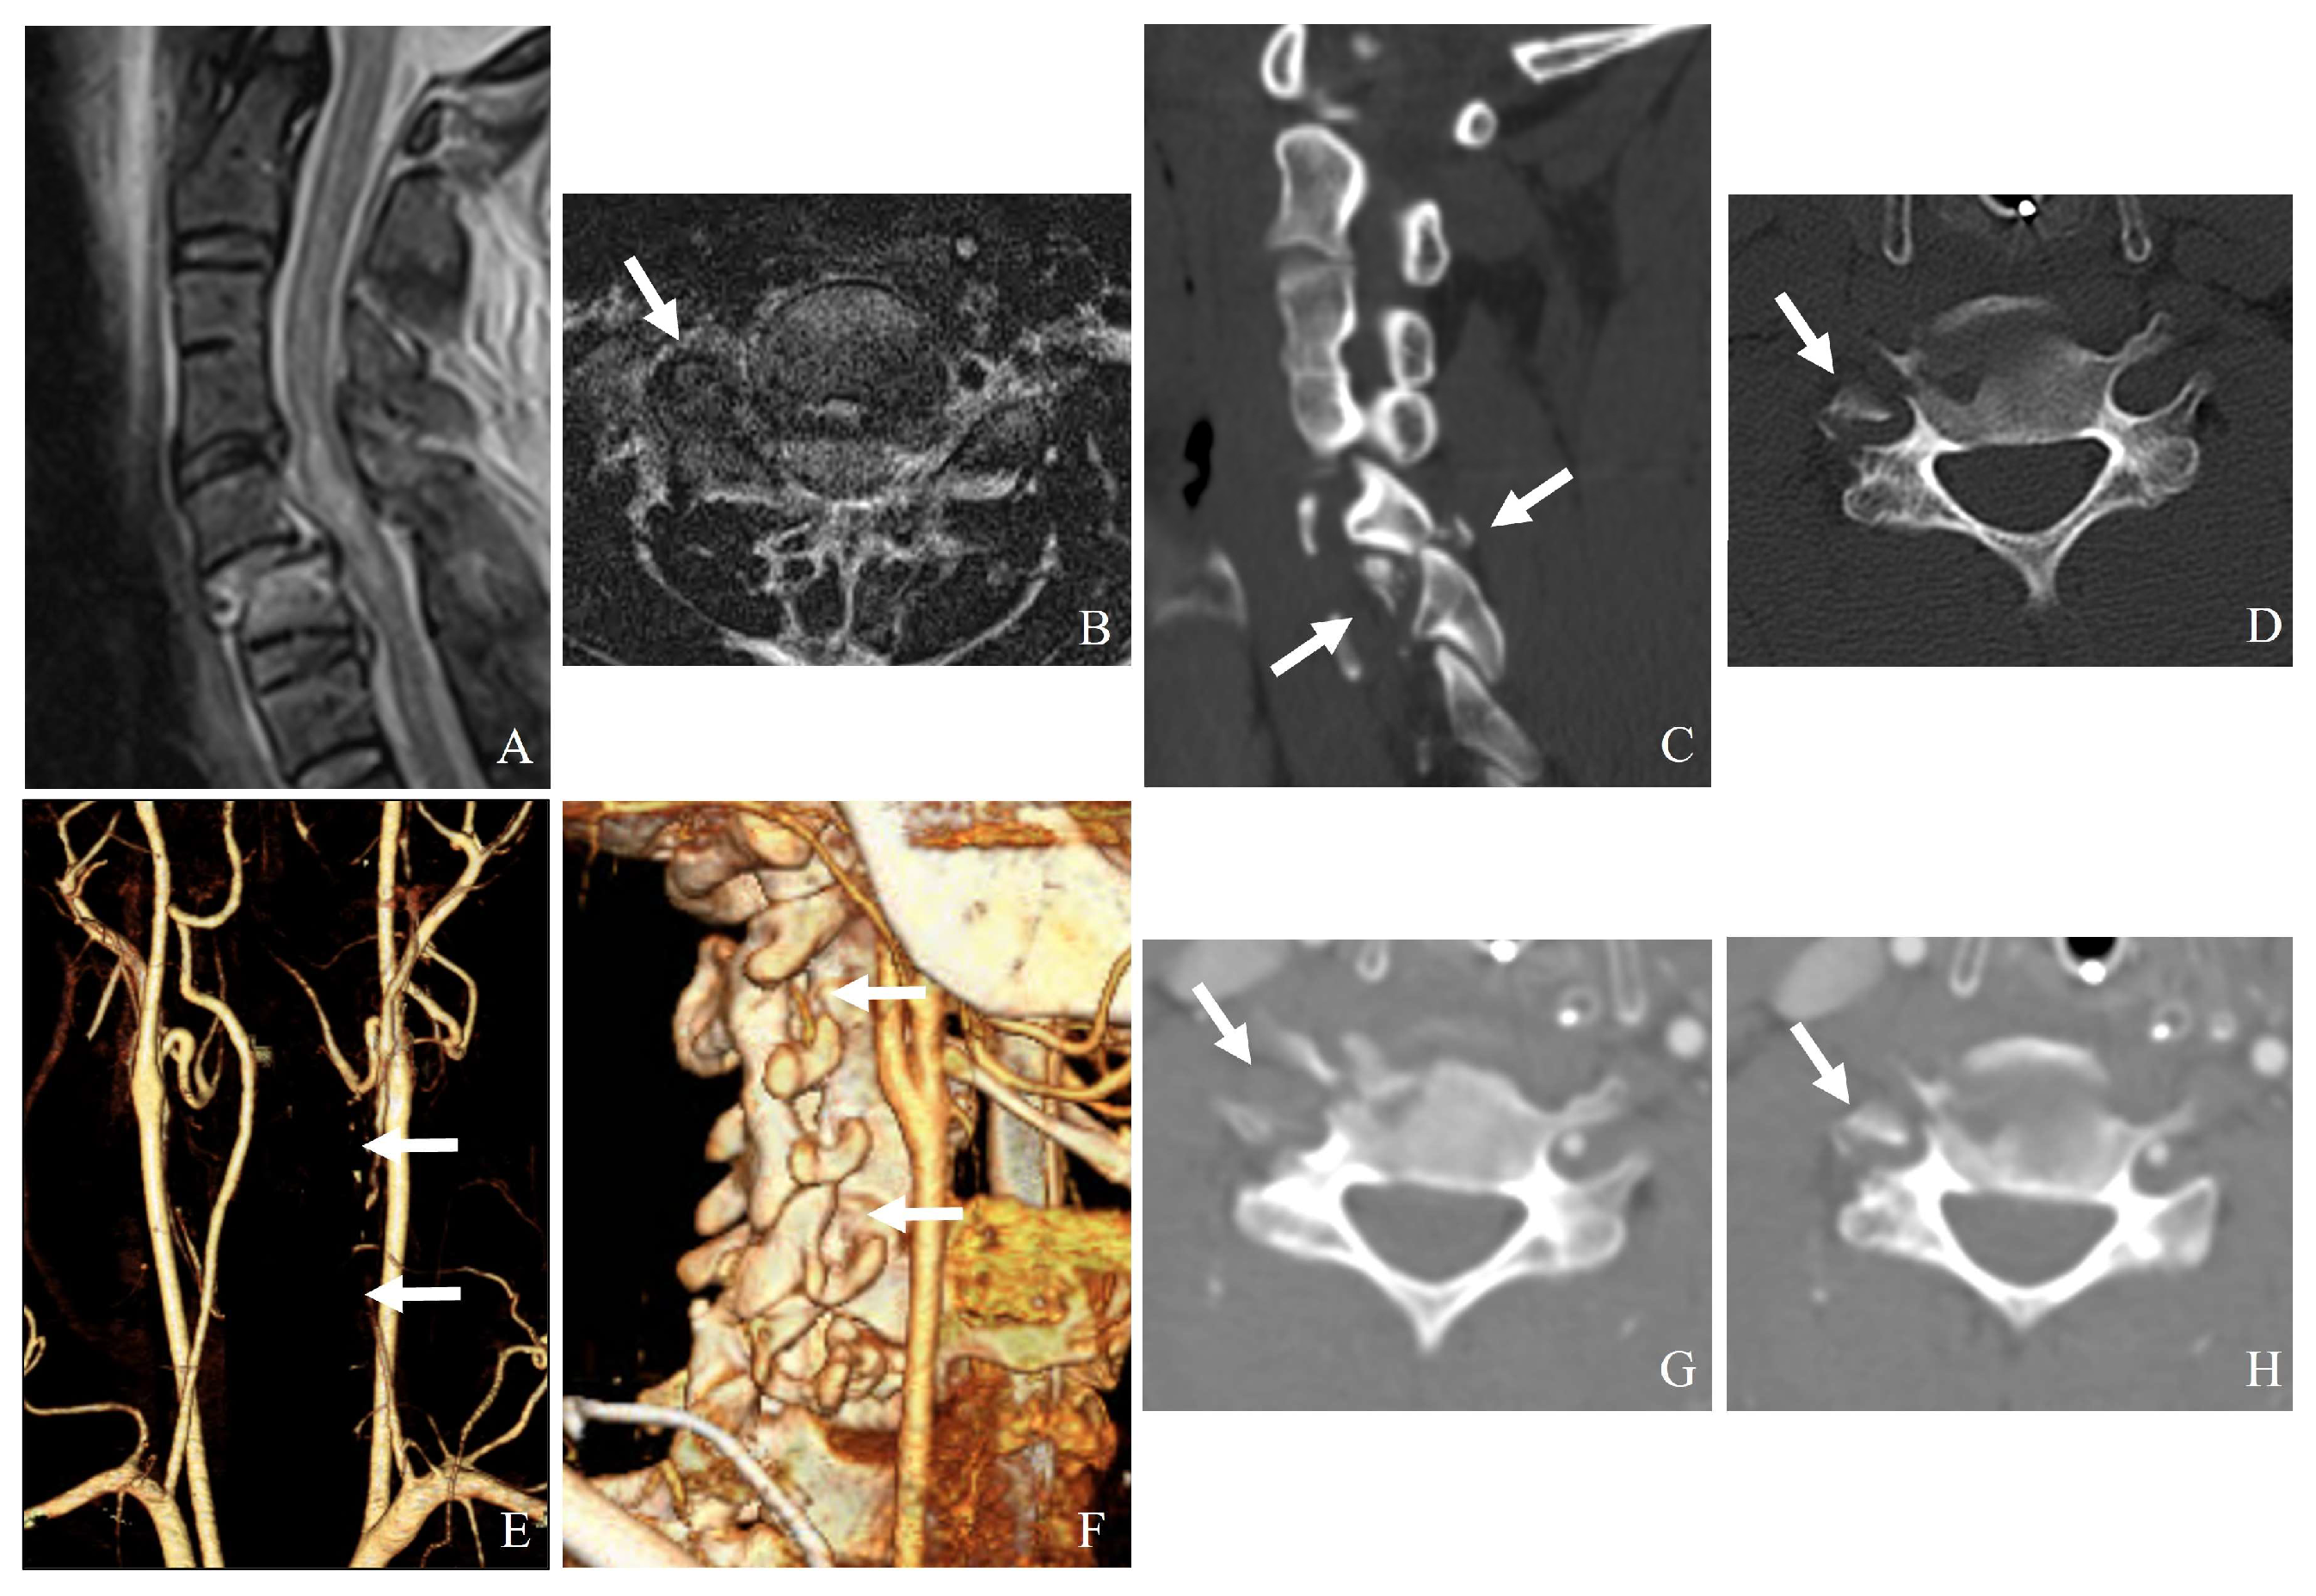

7.2.1. Direct Compression or Stretching

- (1)

- Unilateral or bilateral facet dislocation can cause excessive rotational and translational forces on the vertebral artery, particularly at C3–C6 levels.

- (2)

- Perched or locked facets can lead to excessive stretch or kinking of the artery within the transverse foramen.

- (3)

- Fracture of the lateral mass or pedicle can lead to direct bony impingement on the vertebral artery (Figure 8).

7.2.2. Occlusion from Displacement or Thrombosis

7.2.3. Laceration or Dissection

- A facet fracture extending into the transverse foramen may directly lacerate the vertebral artery.

- High-energy trauma can cause intimal tears, leading to dissection and secondary stenosis or occlusion.

7.3.2. Imaging [13,14,15]

- CT angiography: The gold standard for detecting vertebral artery injuries (Figure 9).

- Magnetic resonance angiography: Useful for assessing arterial dissection and thrombus formation.

- Digital subtraction angiography: The most sensitive but invasive method.